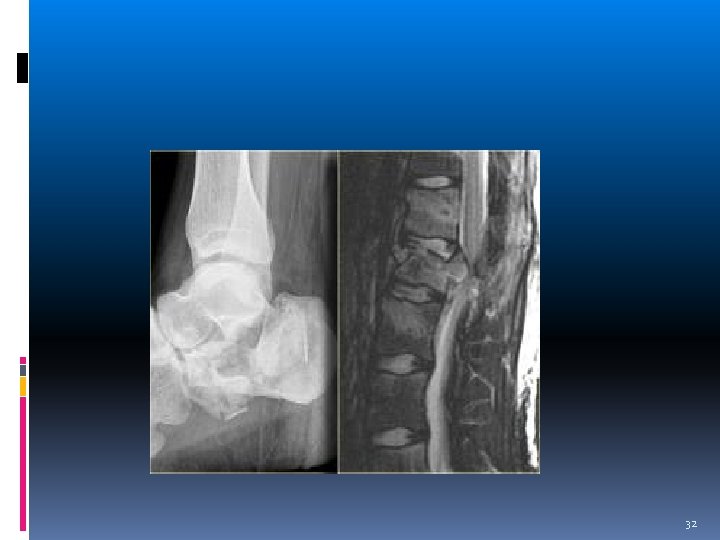

Imaging AP x ray: interpedcular widening(burst fx), Increased interspinous process distance(damage of PLC) Lat x ray: kyphotic deformity(cobb angle), vertebral collapse, PVB 29

% Anterior Height Loss=A 1[(a'+a")/2] x 100 % Posterior Height Loss=P/[(p'+p")/2] x 100 30

PVB 31

32

CT scan Comminution of vertebral body Retropulsed fragment(size, location) Post element fx Helical CT scan choice in polytrauma pt 33

Burst fx 34

MRI Disc herniation Epidural hematoma Lig injury(PLC) -fat suppressed T 2 -weighted image(STIR) Intrasubstans alteration of spina cord(myelomalacia) SCIWORA Gun shot(contraversial) 35